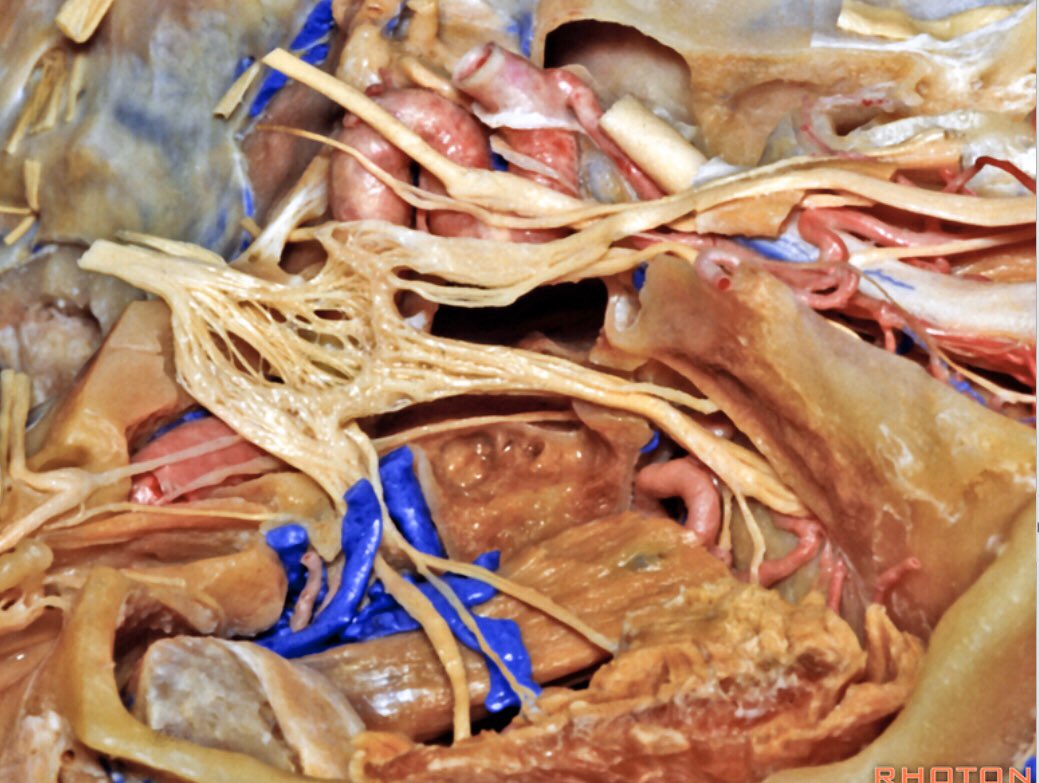

Rhoton somehow got his hands on the Reality Stone. That’s the only explanation for these dissections